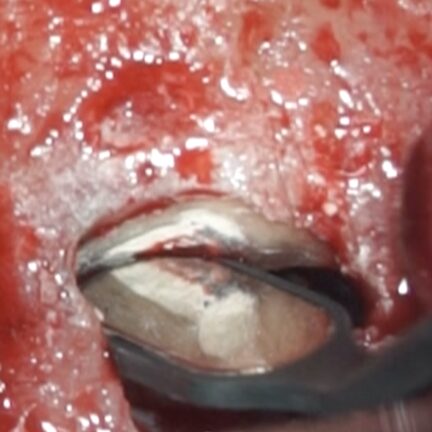

• 歯根端切除術で摘出した歯根と肉芽組織、黄色い色をした菌塊(細菌のコロニー)が多数見られました(黄色丸内のつぶつぶ)。これが非治癒の原因、根尖孔外に飛び出した感染源です。

• 青色の細菌の染め出し液で感染源のイスムスが発覚(青矢印)。根管治療で殺菌が届かない場所です。

• イスムスを削除しながら逆根管形成を行い、お薬(バイオセラミックパテ)を充填したところ(黄色矢印)。

• もう少し歯根を切断すると、イスムス(黄色矢印)が出てきました。感染源です。

• MB1ごとイスムスを超音波の器具で取り除いているところ。

• 未処置の感染部分の除去後、お薬(バイオセラミックパテ)を充填したところ。